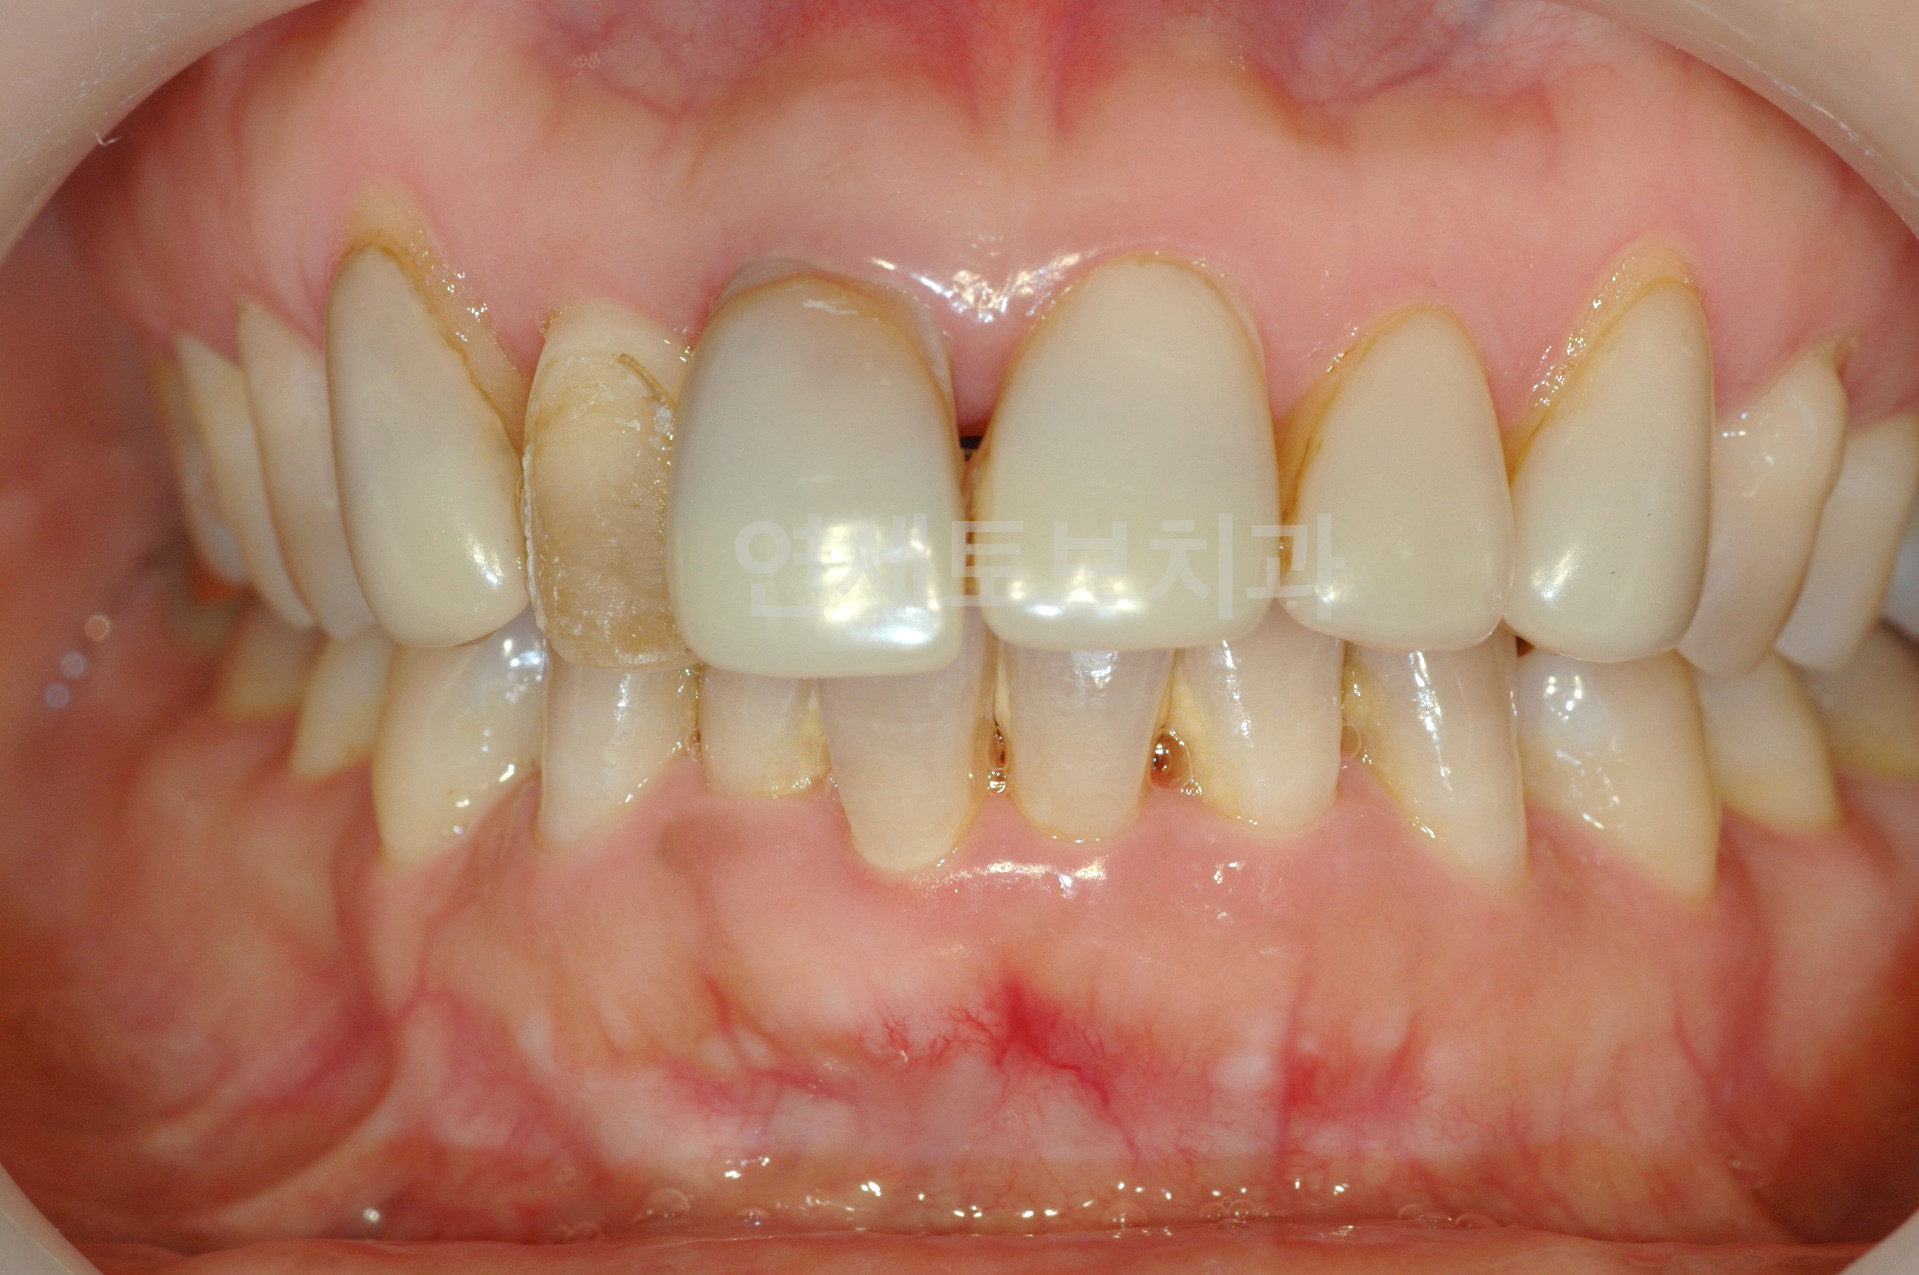

Before

라미네이트 시술 전

After

라미네이트 시술 후